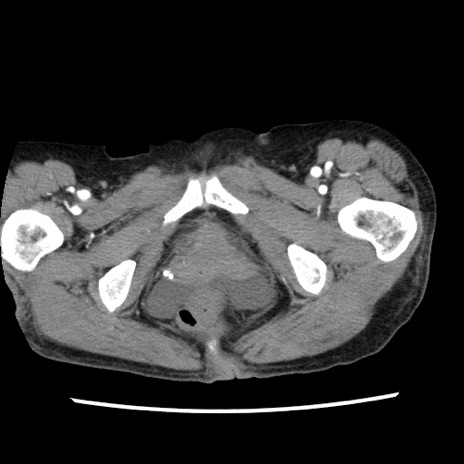

矢状断像

【症例】80歳代女性

【主訴】腹痛

【現病歴】8時間前から腹痛あり来院。

【既往歴】糖尿病、脂質異常症、子宮体癌にて子宮全摘術

【身体所見】意識清明・会話良好だが腹痛で苦悶様、全腹部にわたって反跳痛と圧痛あり

【データ】WBC 13600、CRP 0.14、LDH 224、CK 90